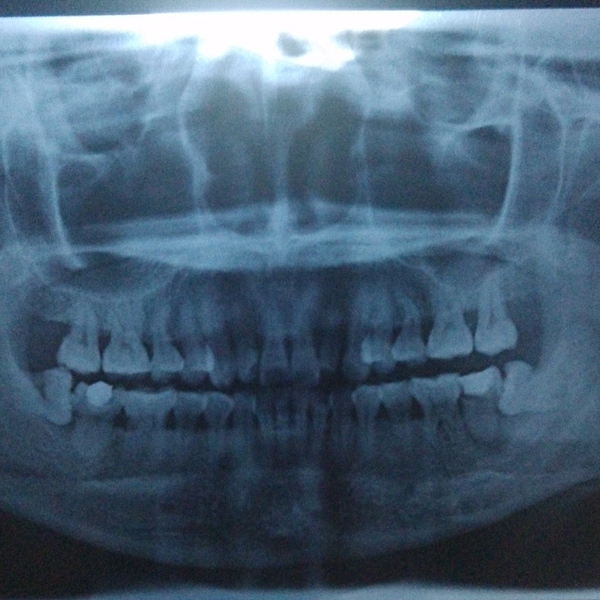

牙齿萌出困难称为"阻生齿"或"埋伏牙"。阻生齿最常见于下颌第三磨牙,俗称智齿,此牙萌出年龄在18岁前后,由于萌出前其它牙齿都早已站好队列了,等智齿生长出来时,就会受到其它牙齿的排挤,故而萌出困难,形成了阻生齿或埋伏牙,我们称之为"阻生智齿"。

大部分的智齿都应拔除。能早拔就早拔,拔晚了就会引起上述的危害。如果在妇女妊娠期发病会严重影响母子健康。20岁左右的年轻人正是在外地或外国上学的时期,如发生急性炎症,其家长往往会心急如焚,因此建议早早拔出阻生智齿,消除智齿的危害。

首先并不是每个人都有机会萌出全部四颗智齿,如果某一颗没有对生的,有可能会造成对位的口腔黏膜磨损,多见于下位。 其次,阻生智齿一定要拔除。阻生简而言之就是你的口腔骨骼没有给那颗牙留足够的位置,这样智齿就会用把兄弟姐妹往旁边挤的粗暴方式长出来。这个过程中,任何的外界刺激,食物残渣残留都可能造成严重感染,

这种情况下就一定要先消炎然后拔除。否则以后你每次发烧感冒都可能使智齿感染,反过来也一样。 一般来说阻生智齿拔除不是大手术,上牙比下牙好拔除,但依据你的牙齿状况,过程可能持续10到15分钟,一定会打麻药,麻药负责你那半边脸的痛感缺失。手术过程中首先要划开牙龈,然后非常可能用到锤子和其他工具把牙撬出,或如果你的牙形比较细长,可能直接敲碎拿镊子夹出。手术风险:如果你的牙根非常长,长到和其下的神经有粘连,可能导致局部的永久性麻痹。术后:每个医生都会告诉你多久拿掉填充物多久可以刷牙。